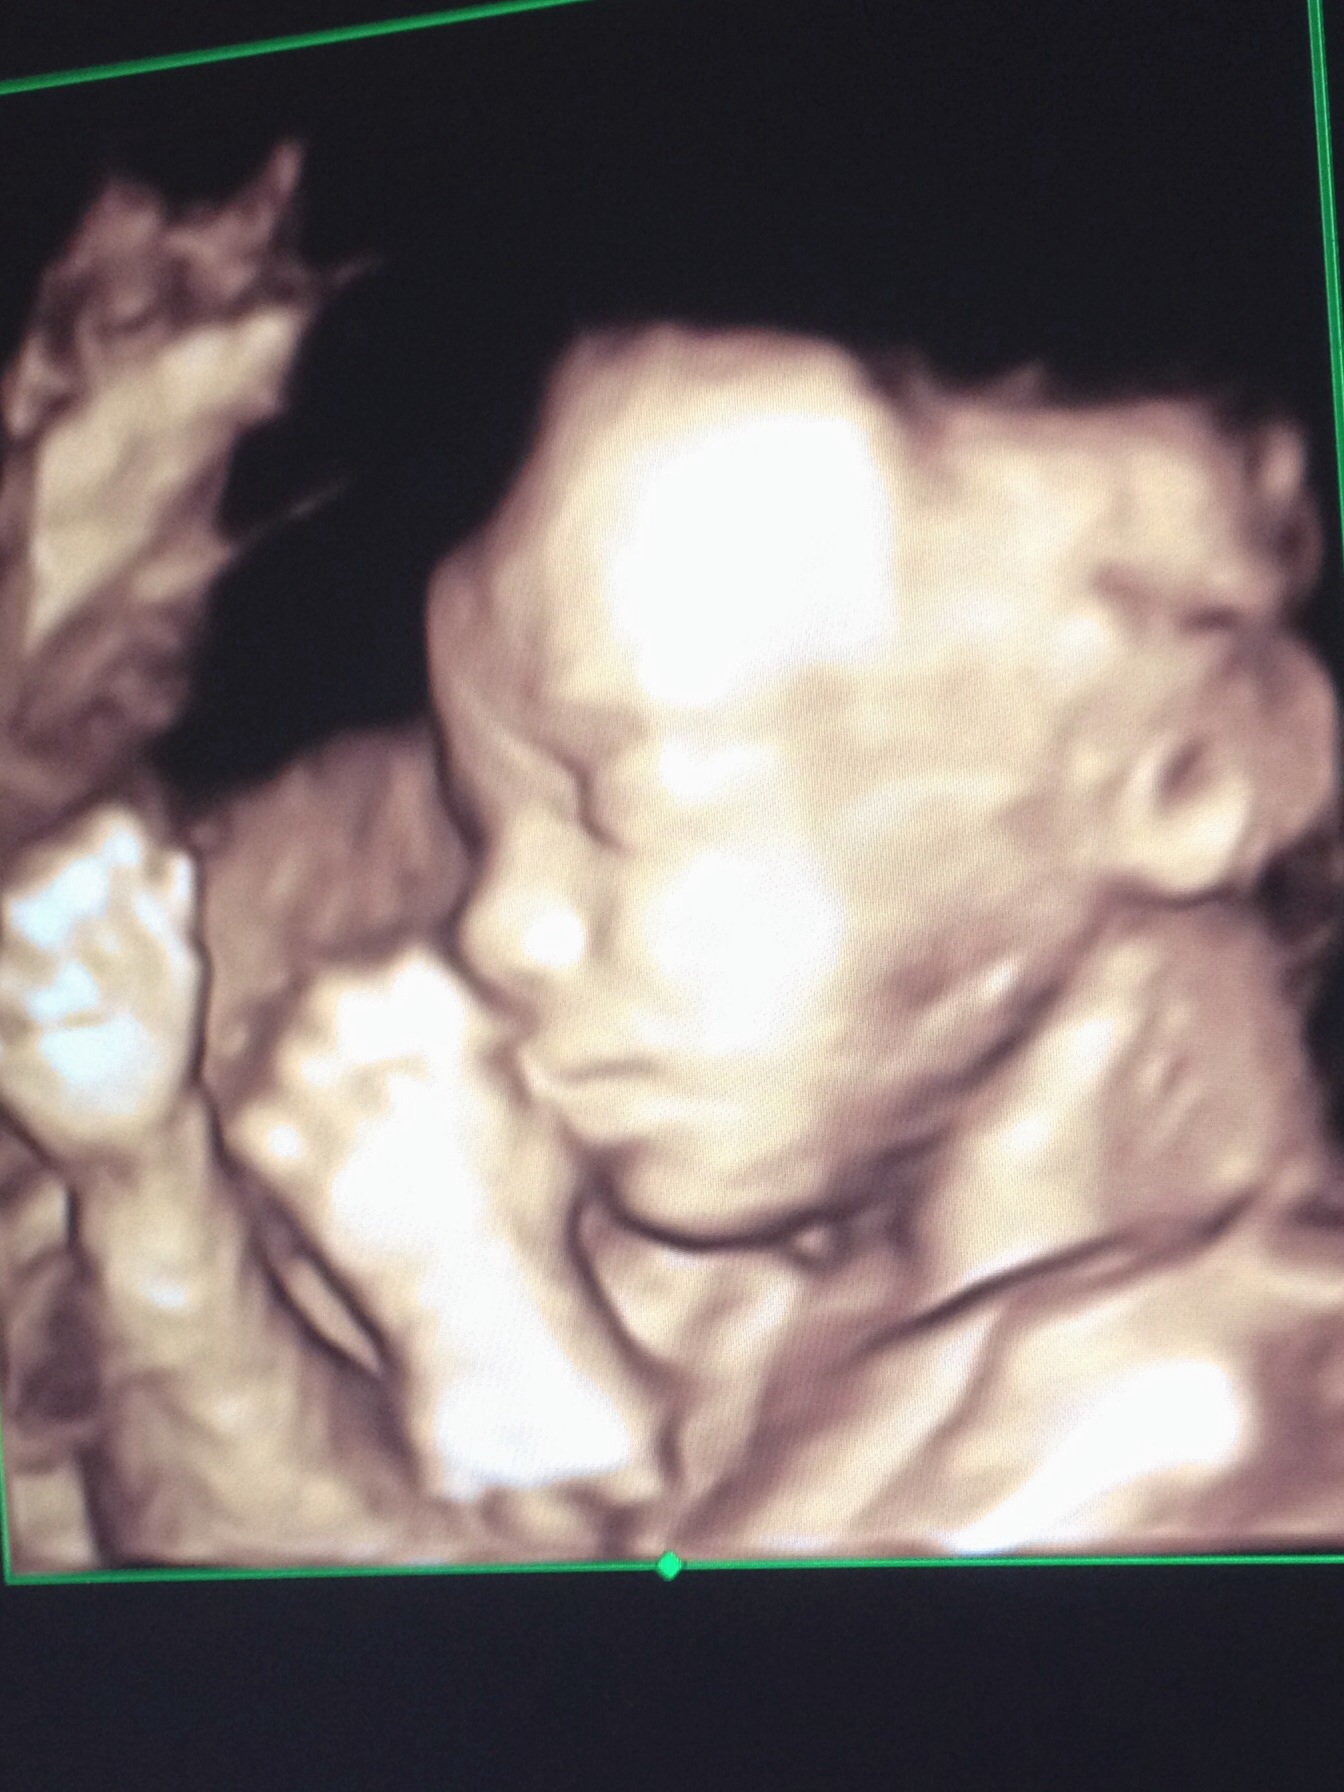

But that's a pretty cute picture of your LO

Here's mine